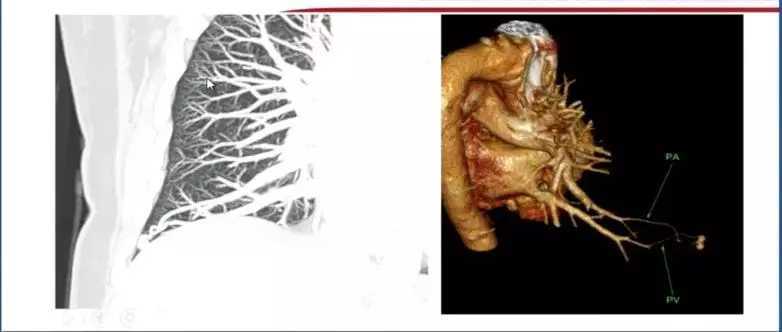

2. 动静脉畸形

肺动静脉畸形经过通过影像技术进行增强处理后诊断明确。

图3 肺动脉畸形

通常情况下,肺细胞瘤需与错构瘤进行鉴别诊断,在进行最大密度投影处理后,CT可见肺细胞瘤对周围血管有推移作用。经过影像后处理,可以通过进一步判断肺结节与附近病变和周围血管的关系进行诊断。

图5 图4-5 CT及处理后图像对比,可明确血管推移,进行诊断

图6 三维图像重建图像,此类情况需与肺内肉瘤和小细胞肺癌进行鉴别,嘱患者保持每3个月随访一次